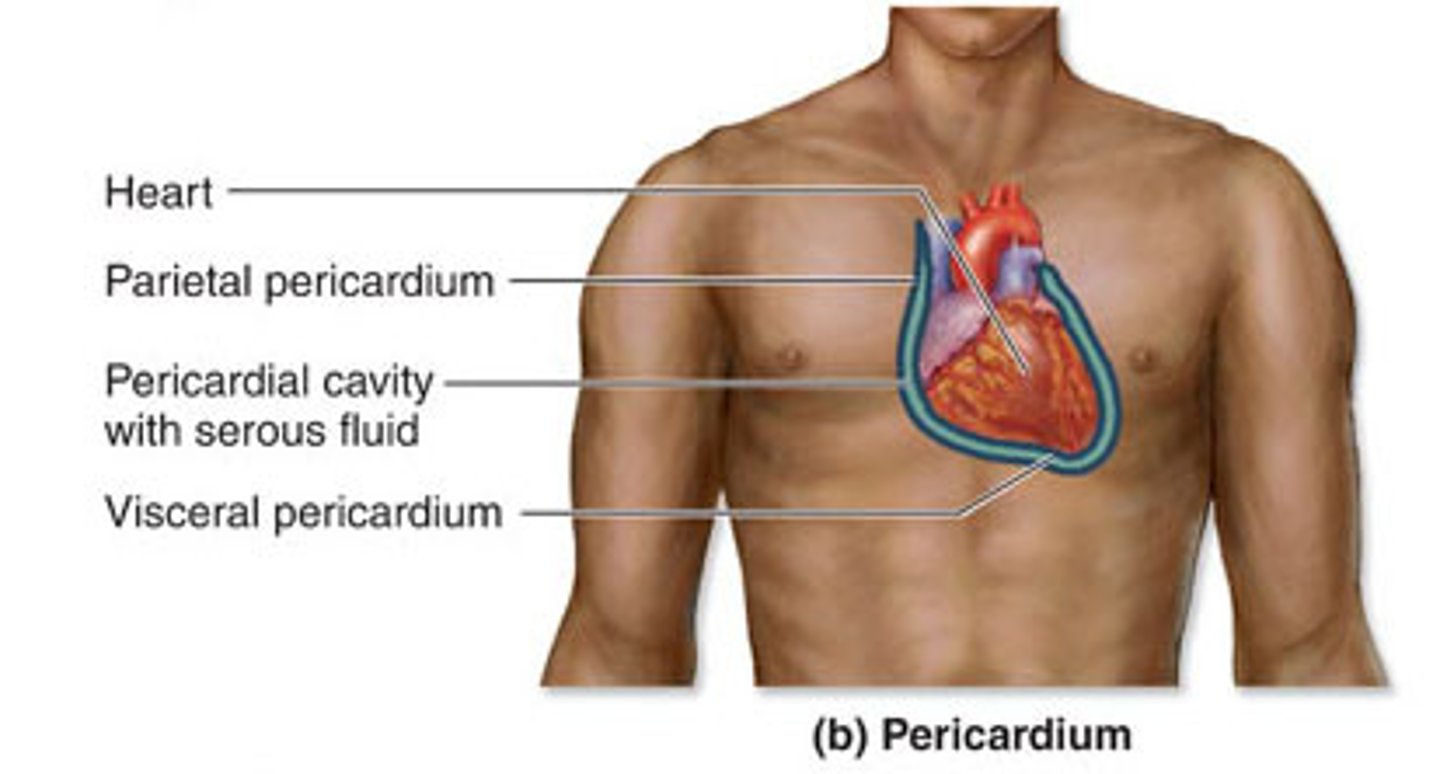

Jakie rodzaje osierdzia wyróżniamy?

surowicze i włókniste

osierdzie surowicze

serous pericardium

Z jakich części składa się osierdzie surowicze?

z blaszki trzewnej i ściennej

blaszka ścienna osierdzia surowiczego

parietal layer of serous pericardium

Gdzie znajduje się jama osierdzia?

między blaszką ścienną i trzewną osierdzia surowiczego

jama osierdzia

pericardial cavity

Co znajduje się w jamie osierdzia?

płyn surowiczy umożliwiający ślizganie się blaszek osierdzia

osierdzie włókniste

fibrous pericardium

Co otacza osierdzie włókniste?

od zewnątrz osierdzie surowicze